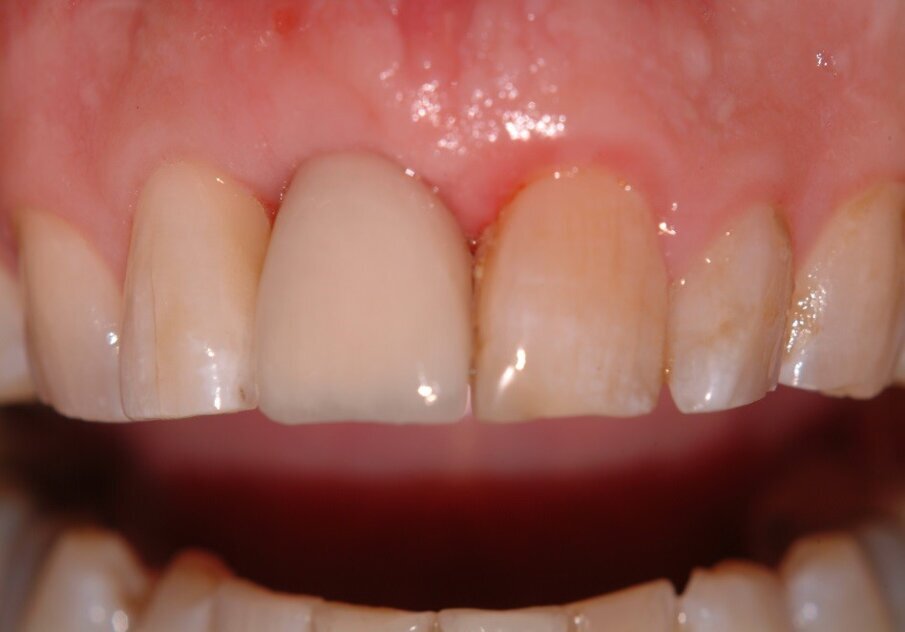

Patient RR was a healthy non-smoking 44 year old male who presented with a complaint of an unaesthetic upper right central incisor with extensive recession showing a large amount of darkened labial root surface. The situation was worsened by a high smile line and a porcelain crown contrasting dramatically with the root colour. He had had periodic swelling at the apical part of the recession over a long period. There was a history of trauma in his teens leading to root canal treatment and a crown, and subsequent apicectomy in his 20s. Clinical examination revealed an otherwise periodontally healthy, well looked-after mouth. (Fig. 1, 2, 3)

Diagnosis was of endodontic failure and possible root fracture leading to loss of labial bone and soft tissue.